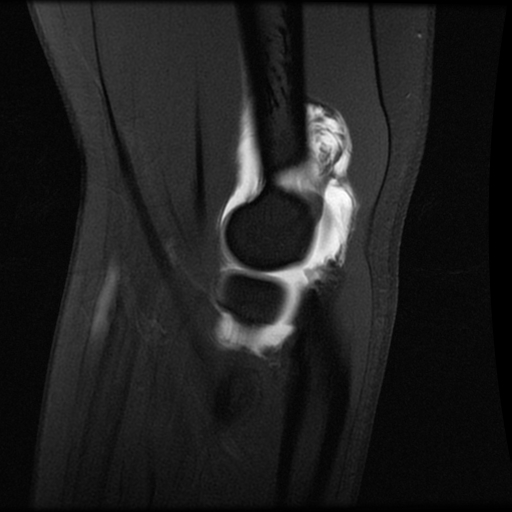

An MRI arthrogram exam is an imaging study. It is used to take detailed pictures of your joints. MRI stands for magnetic resonance imaging. This exam has 2 parts. First you will have an arthrogram and then an MRI. This 2-part exam shows more details of your joint than an MRI by itself. It will help your healthcare provider decide which treatment is best for your medical condition.

- Joints such as knee, hip, and shoulder are made up of 2 bones that fit closely together. Other tissues (cartilage, tendons, and ligaments) support and cushion your joints. An MRI arthrogram helps your doctor see small tears or other problems in these tissues. The results of this exam will help guide your treatment. It will also help your doctor keep track of problems in your joint.

Part 2: The MRI

- You will lie on a sliding table. The MRI technologist will help you get into position for the exam.

- A device called a surface coil will be placed around the joint that is being examined.